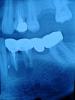

bilal Опубликовано 9 апреля, 2013 Поделиться Опубликовано 9 апреля, 2013 Как Вы думаете, есть ли надежда на успешное лечение консервативным методом данной кисты. Зуб 3.5 - прошел оба канала, промыл гипохлоридом натрия, заложил кальций и закрыл цементом. У корня клыка есть кусочек силера или гутты. Помешает ли он, если его там оставить? Ссылка на комментарий

Денис481 Опубликовано 9 апреля, 2013 Поделиться Опубликовано 9 апреля, 2013 (изменено) по-моему там проблема еще и с 4 кой разряжение тоже есть,снимать придется,этим лечением сами измучаетесь и толку от него мало будет,и такую кистень вряд ли через каналы пролечите,хотя все может быть....и тот кусок чего то около корня если инфицирован,он будет мешать как источник инфекции Изменено 9 апреля, 2013 пользователем Денис481 Ссылка на комментарий

Kivilgar Опубликовано 9 апреля, 2013 Поделиться Опубликовано 9 апреля, 2013 по-моему там проблема еще и с 4 кой разряжение тоже есть,снимать придется,этим лечением сами измучаетесь и толку от него мало будет,и такую кистень вряд ли через каналы пролечите,хотя все может быть....и тот кусок чего то около корня если инфицирован,он будет мешать как источник инфекцииЧем вас размеры не устраивают? Лучше обратить внимание на периодонтальную щель-карман-рецессию. Ссылка на комментарий

Денис481 Опубликовано 9 апреля, 2013 Поделиться Опубликовано 9 апреля, 2013 (изменено) я не писал что они меня не устраивают,меня не устраивает наличие моста на таких зубах,и качество лечения канала 4 ки,ну по размерам воспаление большое, захватывает 2 зуба,а так все прекрасно Изменено 9 апреля, 2013 пользователем Денис481 Ссылка на комментарий